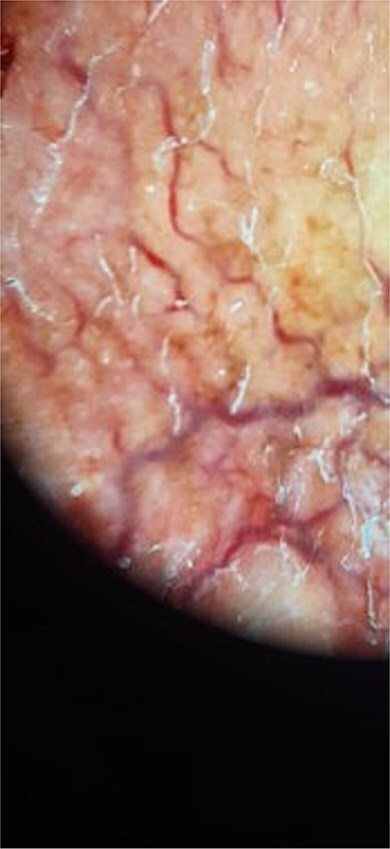

Lupus vulgaris (LV) is a chronic, paucibacillary form of cutaneous tuberculosis. These often-mutilating lesions present a significant diagnostic challenge. We report the case of a 61-year-old patient who presented with a voluminous telangiectatic and ulcerated pseudo-tumoral mass measuring 10 cm in diameter, with a mutilating aspect. Histopathology of the skin lesion revealed granulomatous dermo-hypo dermatitis. Lymph node biopsy showed granulomatous inflammation. QuantiFERON-TB assay was positive, and the established diagnosis was pseudo-tumoral lupus vulgaris. The patient was successfully treated with standard four-drug anti-tuberculosis therapy. This case highlights the importance of a multidisciplinary approach, integrating rigorous clinical, biological, and histopathological correlation for early diagnosis. Appropriate anti-tubercular treatment led to significant and rapid lesion improvement, preventing severe and mutilating complications.